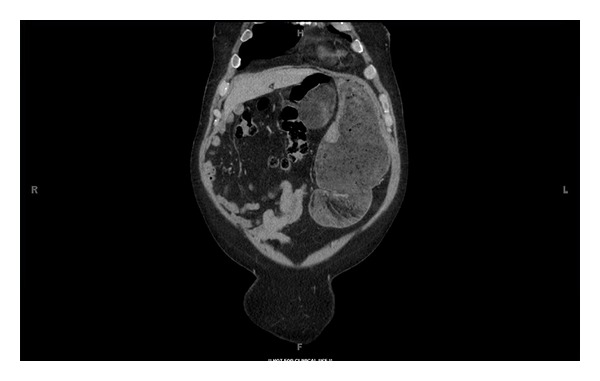

Hematologic studies revealed a leukocytosis of 17,200/mm3. Abdominal radiograph showed a soft tissue density in the left midabdomen. Computed tomography scan of the abdomen demonstrated a 12.1 × 6.4 cm anterior epigastric lesion containing fat and soft tissue, as well as dilation of the stomach and duodenum (Figures 1–3).

Figure 2.

Computed tomographic coronal image showing epigastric mass abutting dilated stomach and duodenum.